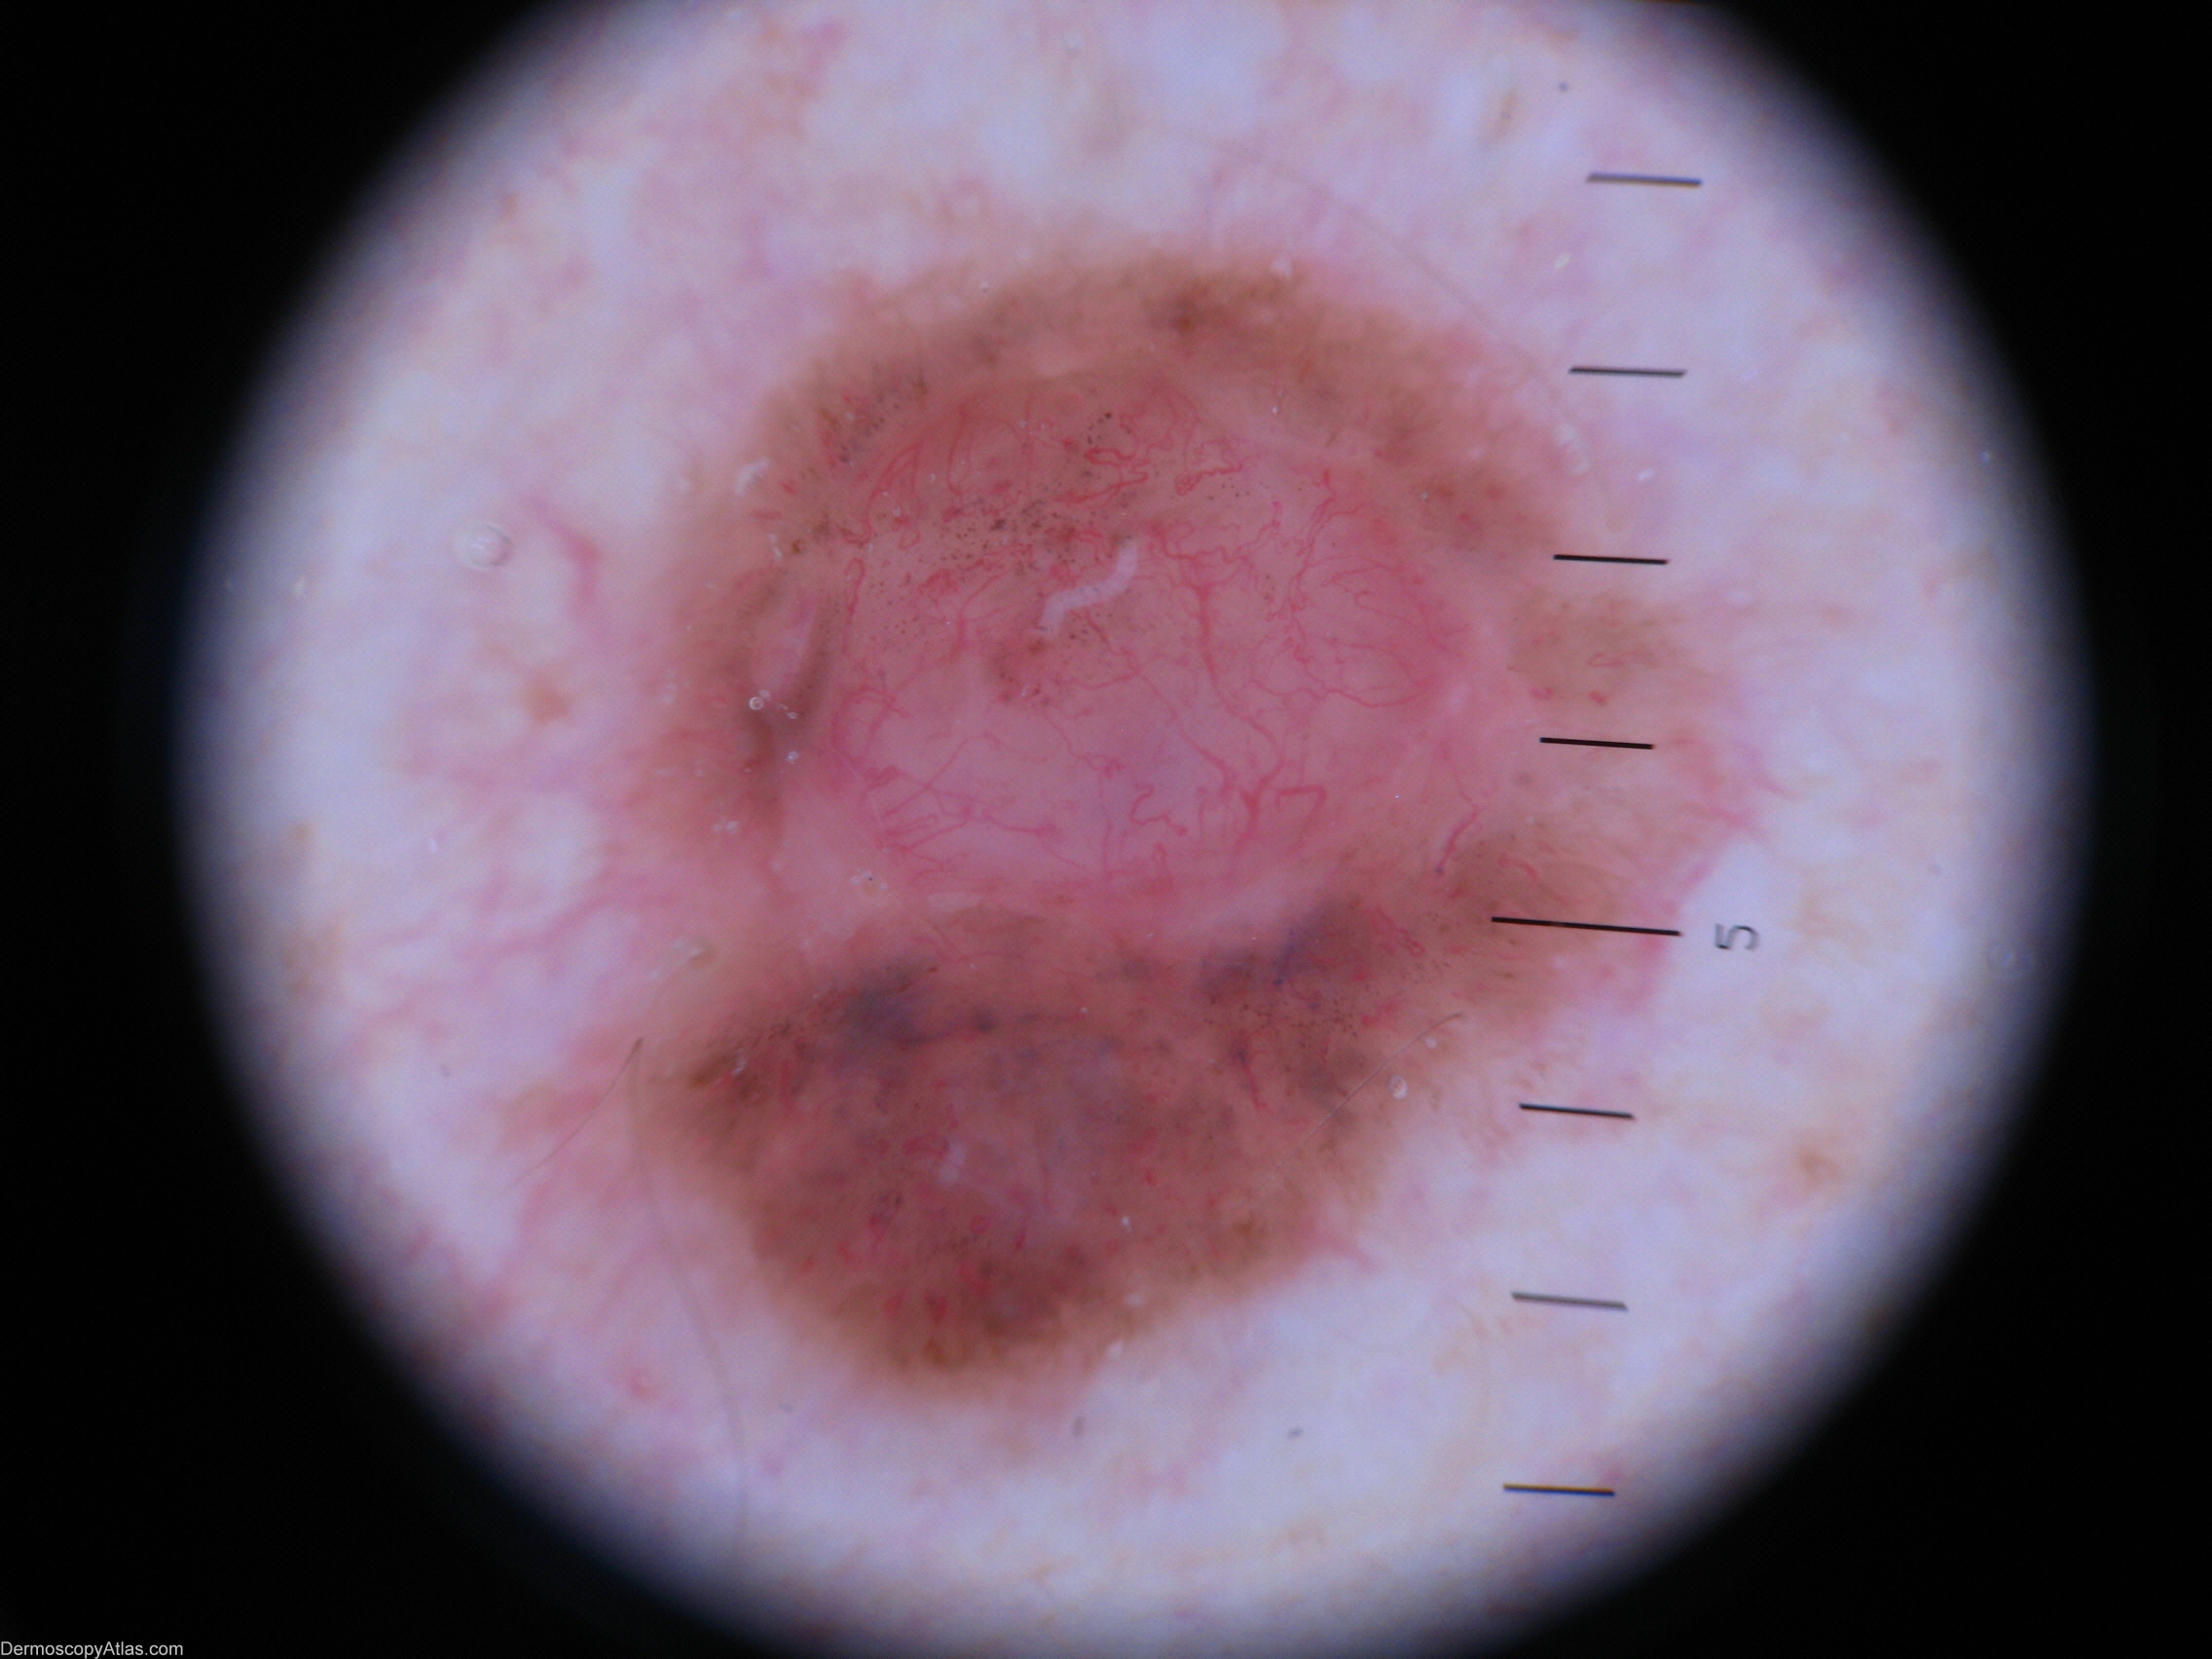

Image Number #2967 (BCC pigmented)

Site: Shoulder

Diagnosis: BCC pigmented

Sex: M

Age: 45

Description: Macro view

Patient was not worried about this lesion until his wife insisted he have it seen to.

It looked nodulocystic and seemed to be arising in a naevus.

Histology. Basal Cell Carcinoma (solid and pigmented)

Supplementary report revealed nearby associated Lentigo simplex.